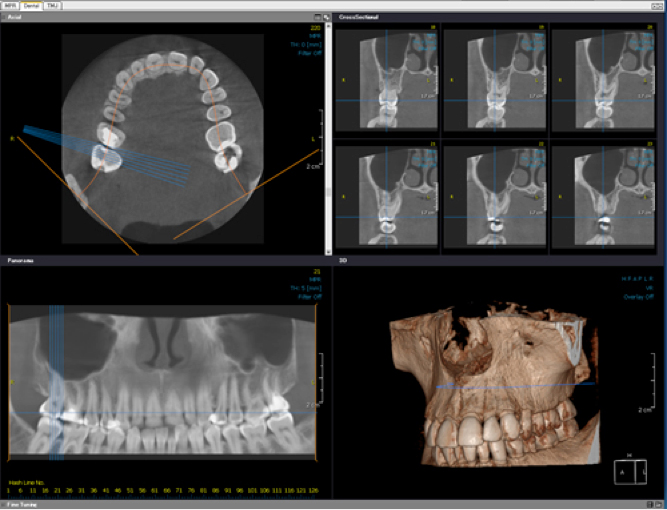

国産の歯科用CTを導入し口腔内を精密に把握

CTを活用することで、より精密なインプラント治療を行います。

CTを活用することで、より精密なインプラント治療を行います。

また、一般治療に関しても、今まで見えなかった深部領域を明らかにすることができるため、より適切な診断、治療が行えます。